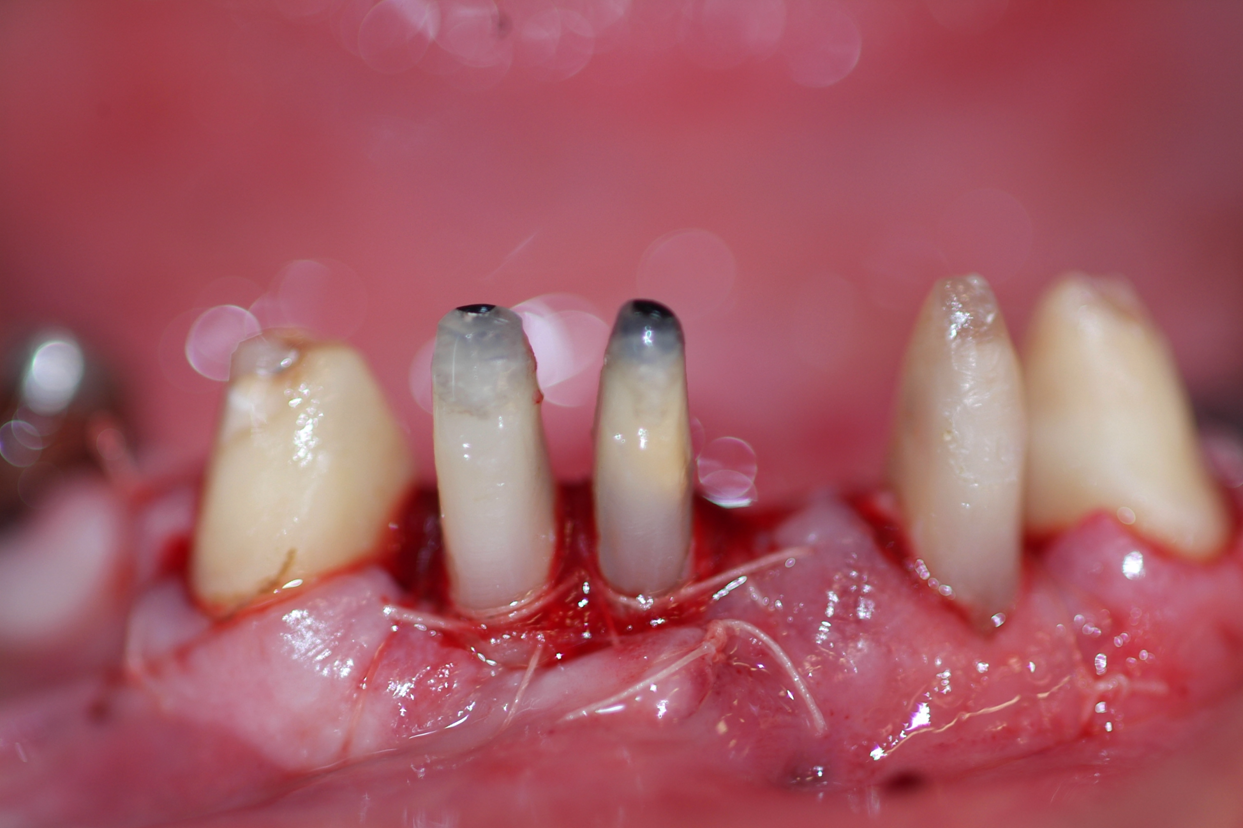

Il paziente chiede il rifacimento protesico di terapie eseguite da oltre 20 anni. Il caso comporta un trattamento multidisciplinare: endodontico, implantologico, protesico e di chirurgia osteoresettiva. Si rimodella l'osso per ridare un corretto profilo osseo e una nuova estetica al sorriso.

Chirurgia osteoresettiva

Riabilitazione orale delle due arcate protesi fisssa in oro ceramica dopo chirurgia osteoresettiva.